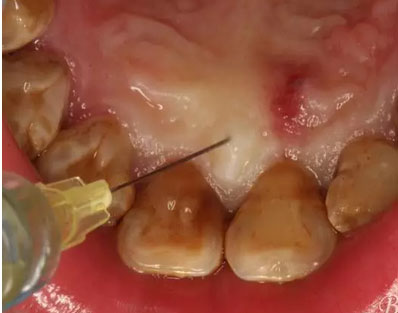

圖6.腭側(cè)無痛浸潤麻醉:腭乳頭發(fā)白。

圖7.11近中的垂直切口